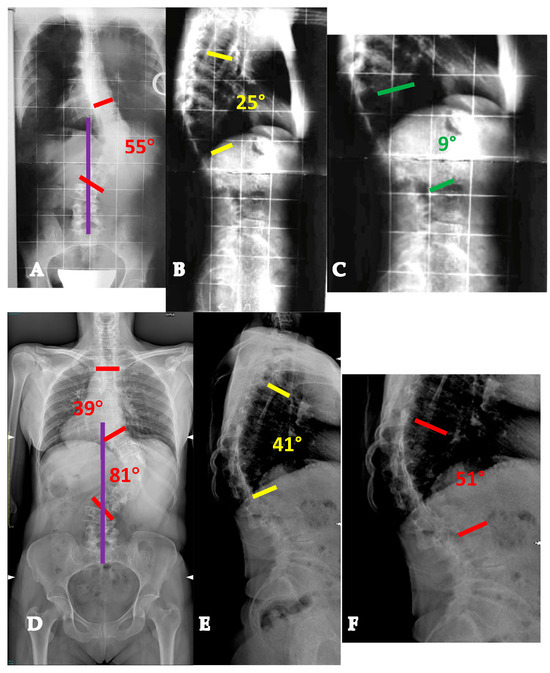

- AdIS 1C: >60 years old. This is infrequent, since patients in this age group more commonly tend to lie in the AdIS 2 group. This group is burdened by an increased stiffness due to an even more frequent anterior column spontaneous fusion, resulting in a less powerful correction both in terms of translation and derotation, with a consequent smaller correction rate and more prominent residual rib hump. However, it must be considered that these patients more commonly present to surgeons because of pain rather than cosmetic concerns. In this view, pain generators should be carefully identified and adequately treated, performing foraminal and/or central decompressions and discectomies where appropriate (Figure 7).